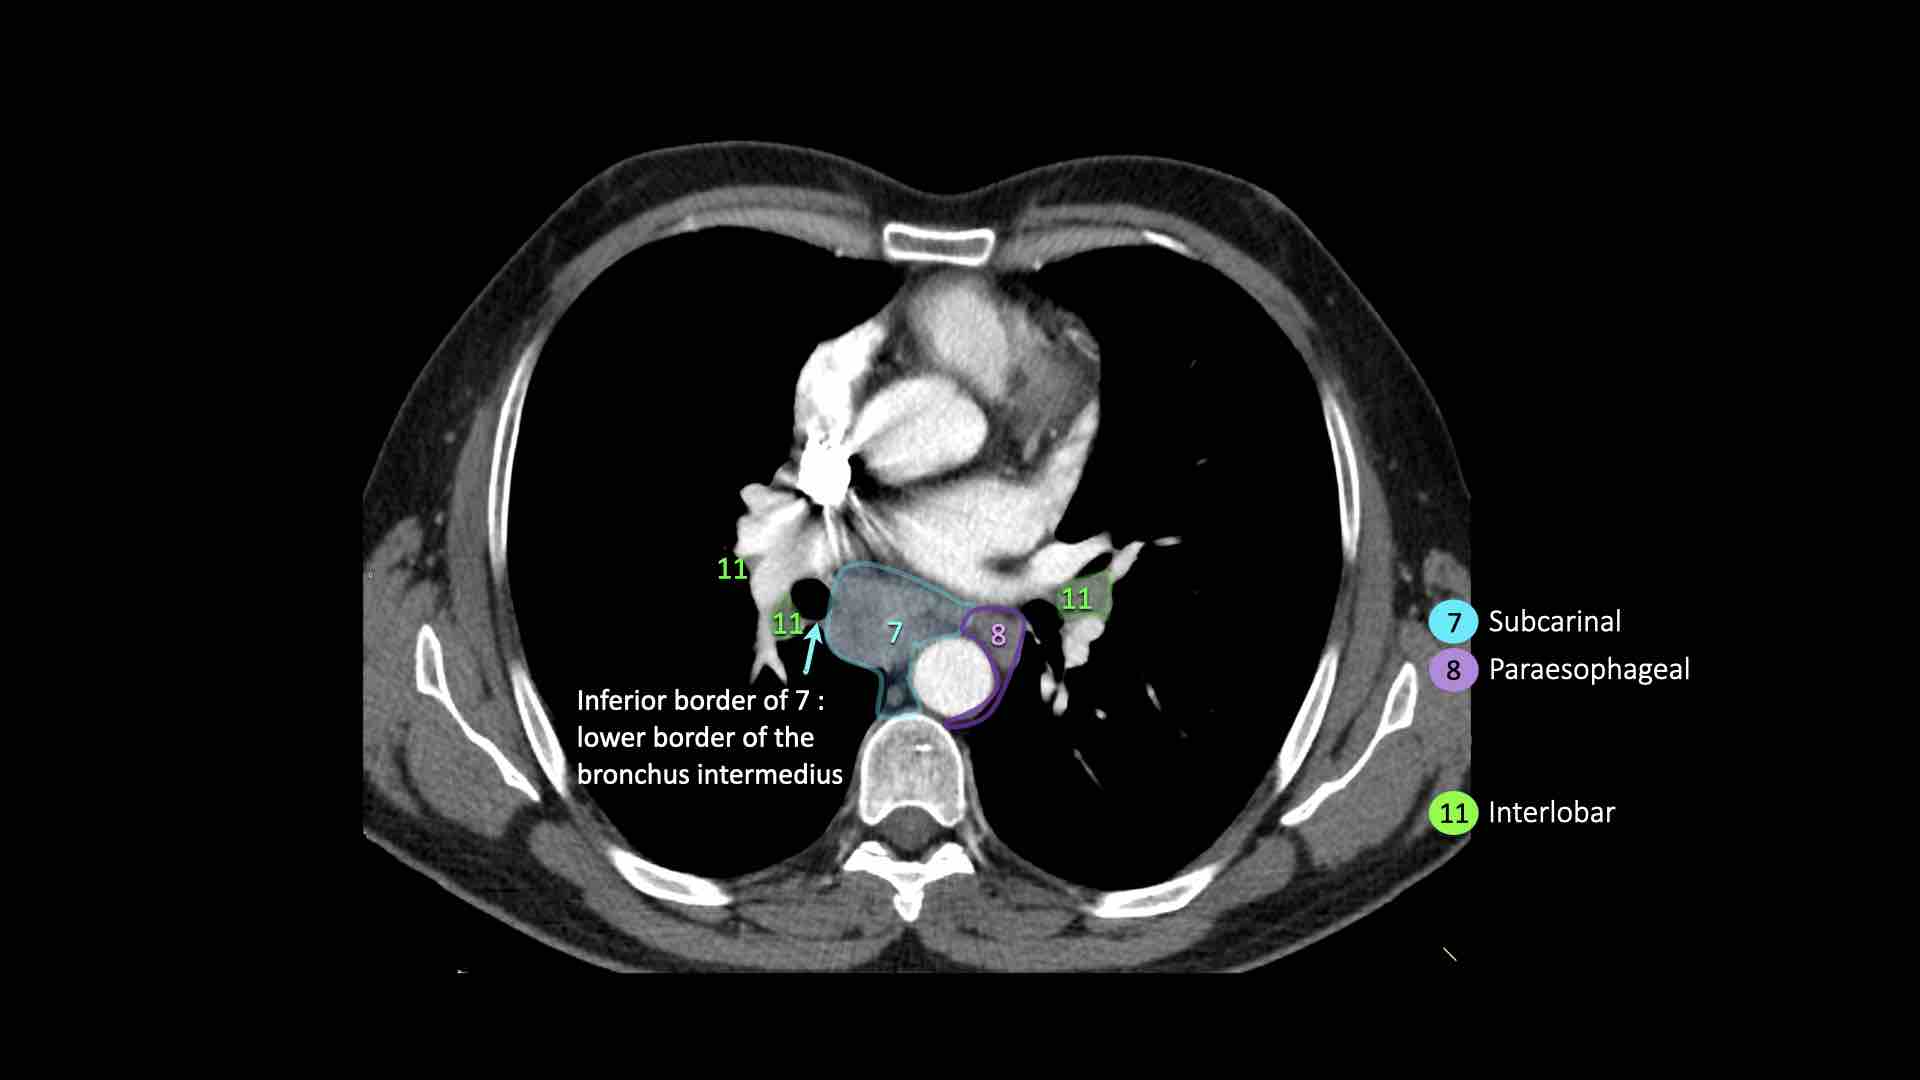

7. Hạch dưới carina

Các hạch này nằm ở phía dưới carina khí quản, nhưng không liên quan đến phế quản thùy dưới hoặc các động mạch trong phổi.

Bên phải, chúng trải dài xuống đến bờ dưới phế quản trung gian.

Bên trái, chúng trải dài xuống đến bờ trên phế quản thùy dưới.

8. Hạch cạnh thực quản

Các hạch này nằm bên dưới các hạch dưới carina và trải dài xuống đến cơ hoành.

Bên trái là hình ảnh dưới mức carina.

Bên phải thực quản là một hạch nhóm 8.